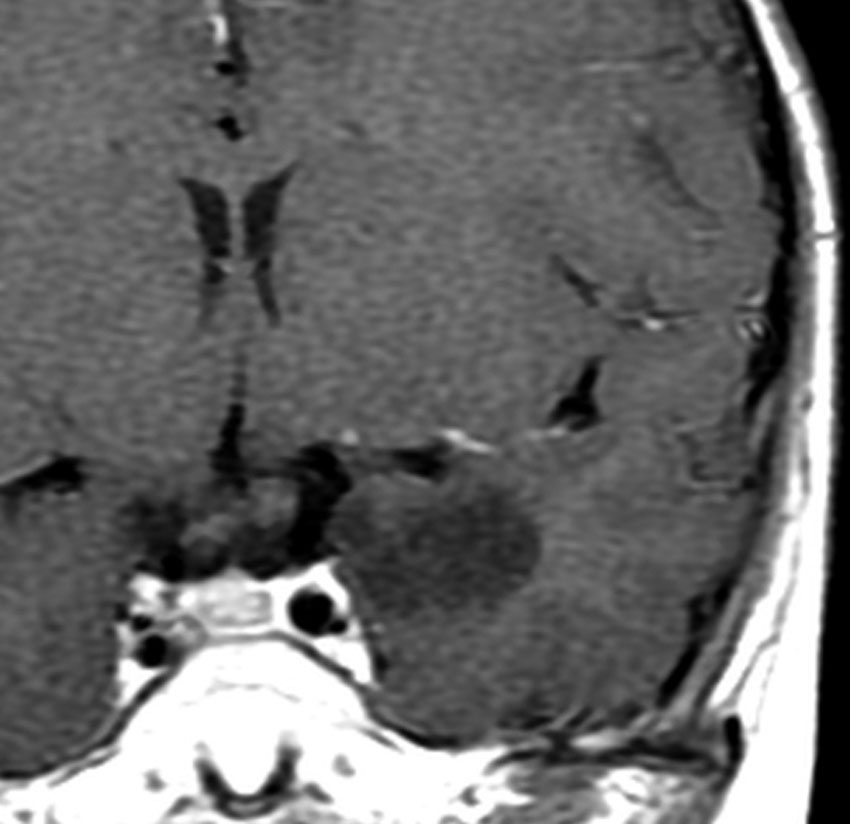

壮年男性の乏突起膠腫 グレード2です。右の運動野(中心前回)に入っているので完全摘出はできません。

前方の上前頭回のわずかな部分摘出をして,手術後に46グレイ23分割の局所放射線治療とテモゾロマイドの併用治療しました。それから,テモゾロマイドを4週間に一回投与して,24コース,2年間続けました。左のMRIは9年後の画像です。腫瘍は消失していないのですが,ずっと同じ状態です (DS disease stablilized)。

乏突起膠腫は予後が良いので,大きな線量の放射線治療は使用したくありません。46Gyは最低線量でしょう。照射の減量分を2年間のテモゾロマイドで補えるかもしれません。でもこの治療方法の確実性は科学的に証明されていません。